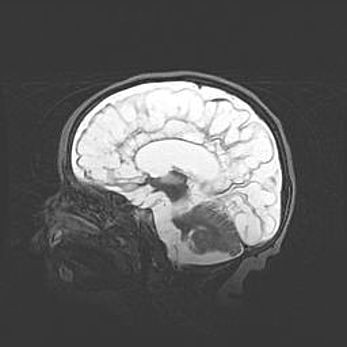

Открытая гидроцефалия.

Возраст: 6 месяцев 15 дней

Вес: 6200 г

Пол: женский

Окружность головы: 41 см

Срок гестации: 38 недель

Гидроцефалия головного мозга у новорожденных – это скопление избыточного количества цереброспинальной жидкости в головном мозге. Ее избыточное скопление в мозге приводит к патологическому расширению желудочков мозга (четырех полостей, расположенных в глубине белого вещества мозга, заполненных цереброспинальной жидкостью и связанных узкими проходами).

Открытый тип гидроцефалии (сообщающаяся) наблюдается тогда, когда нарушен механизм всасывания ликвора в системный кровоток. При этом типе причиной заболевания чаще всего является перенесенные ранее инфекции (например: менингит),  либо же наличие крови в субарахноидальном пространстве.